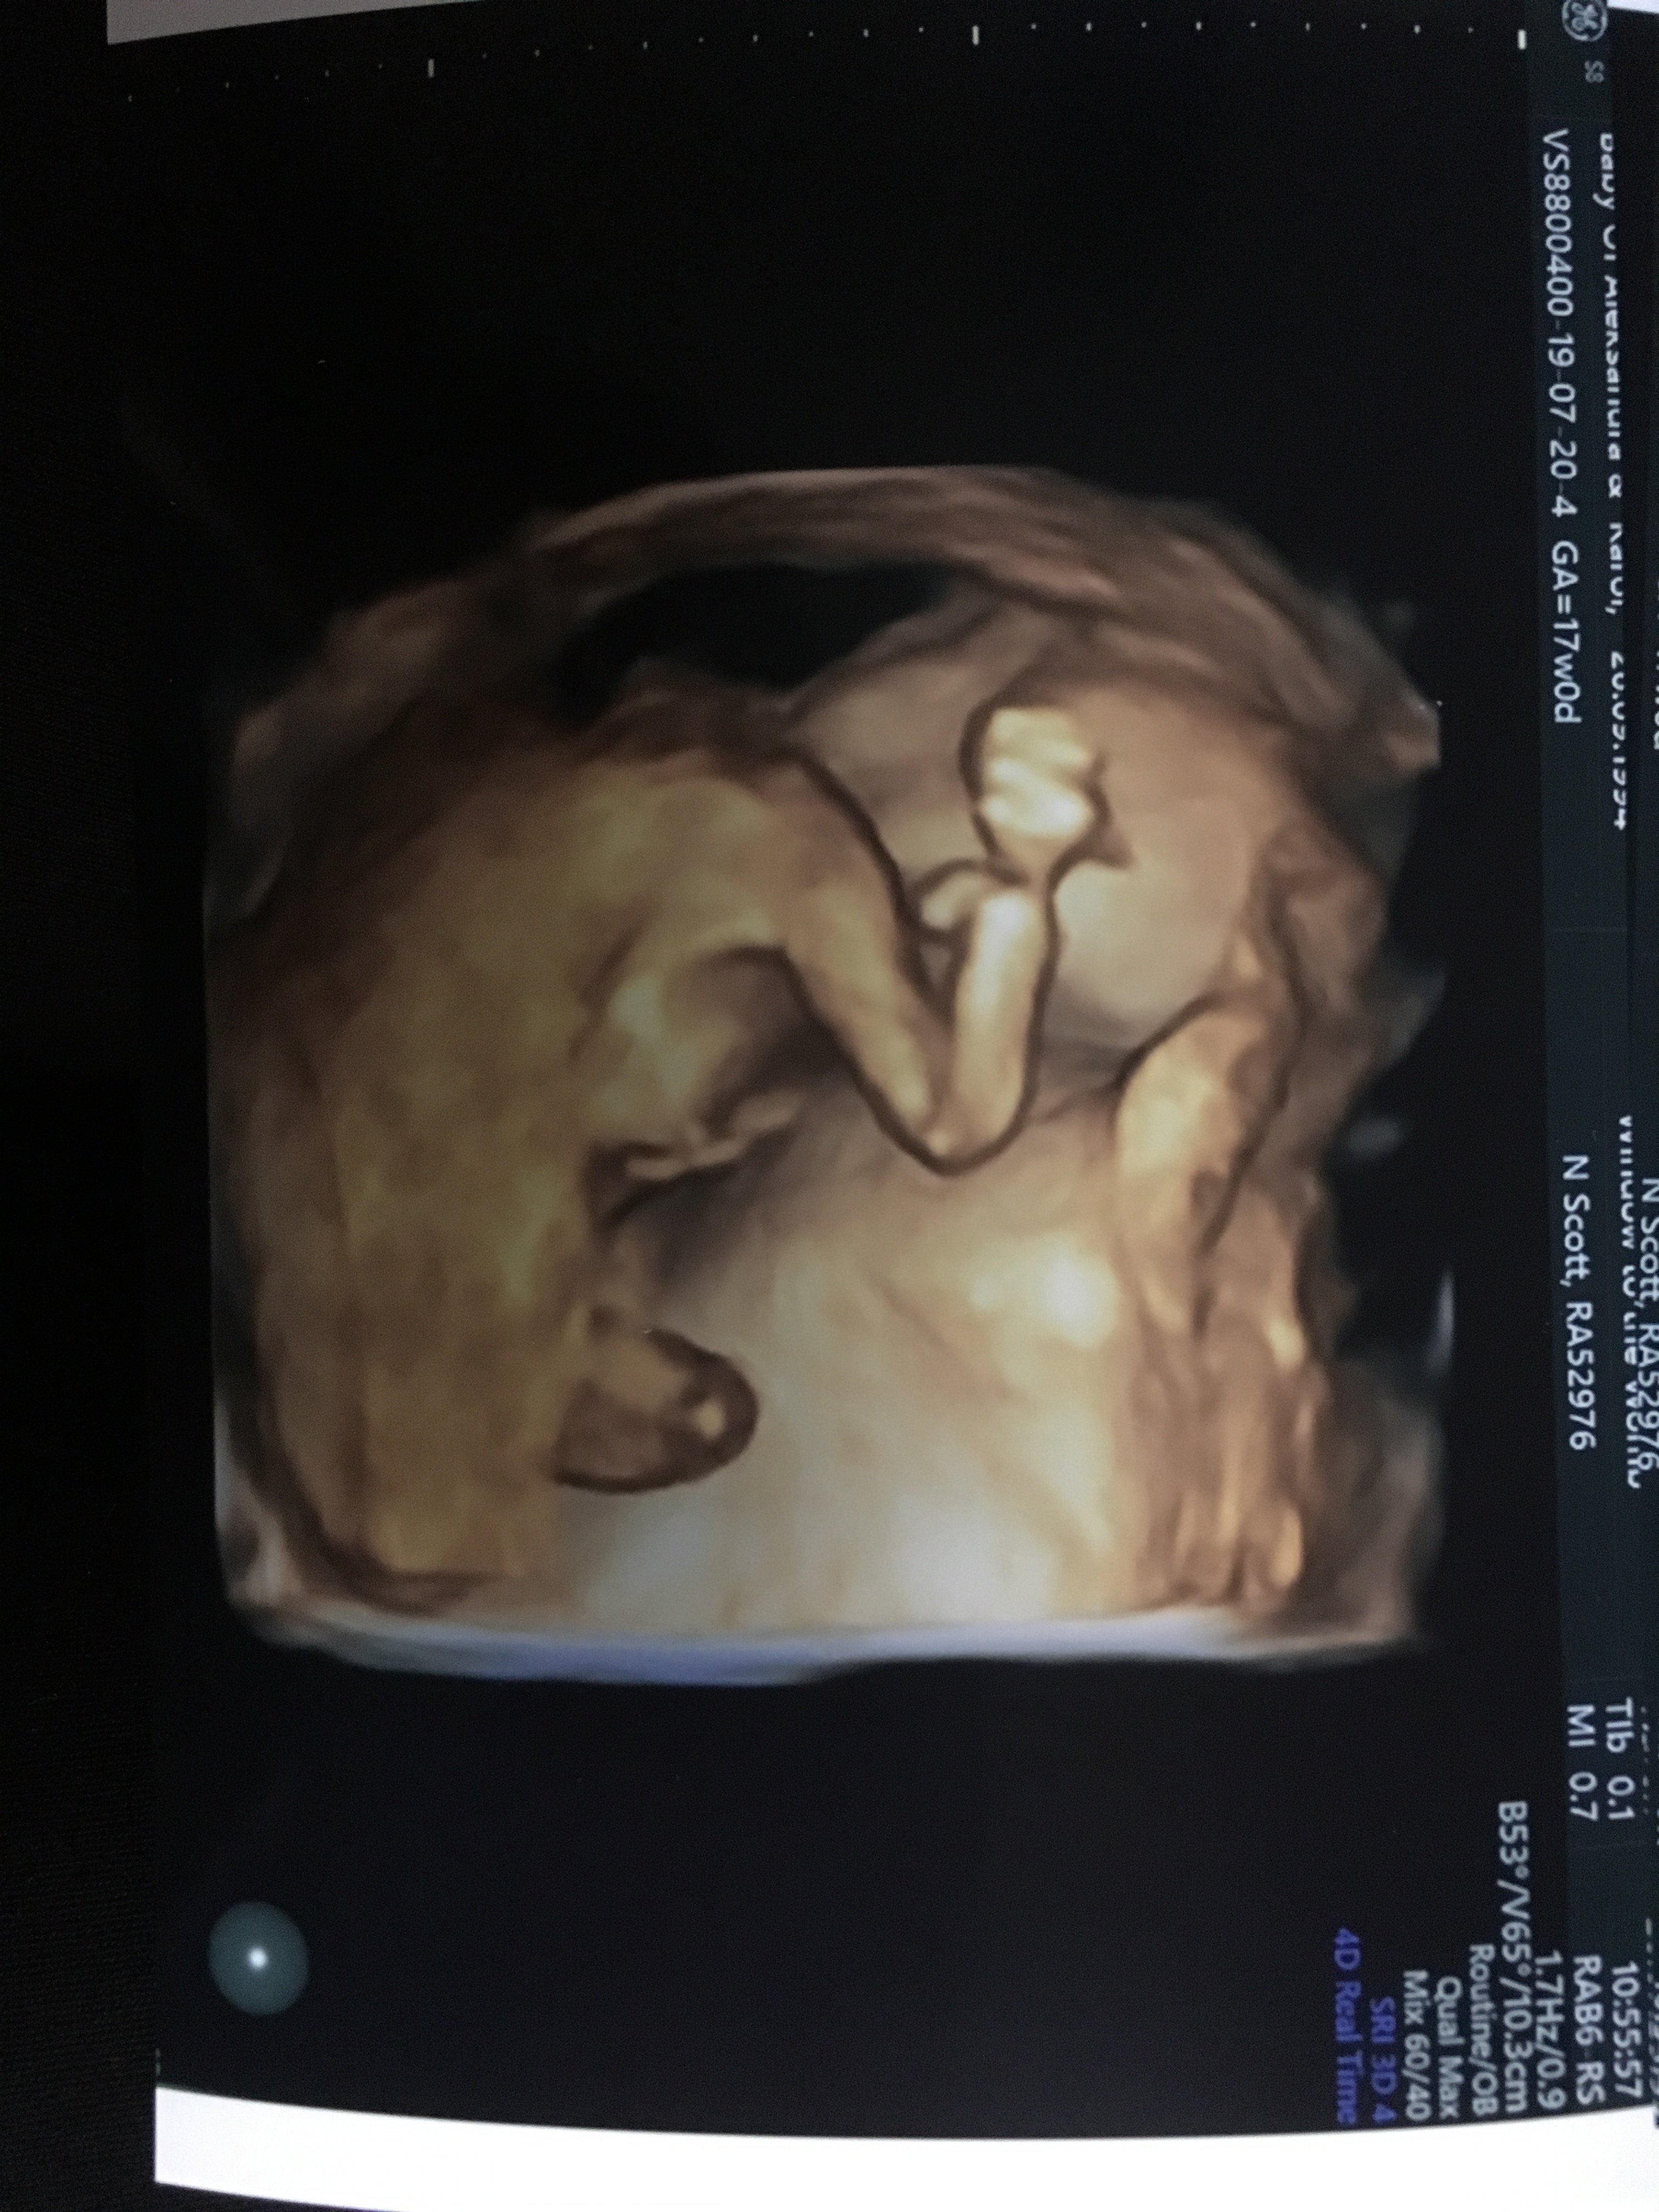

Od dziś czuję ruchy. To moja druga ciąża wiec brzuch mam duży 15 +5tc Zobacz załącznik 1000349